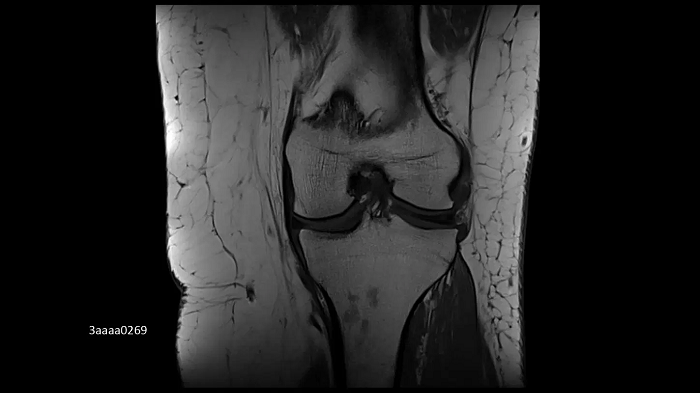

Knee imaging with the new Tx/Rx Knee 18

The new coil provides high-resolution knee imaging as well as a wider coil aperture to accommodate a larger patient population.

Image Credit: University Hospital Tübingen, Germany